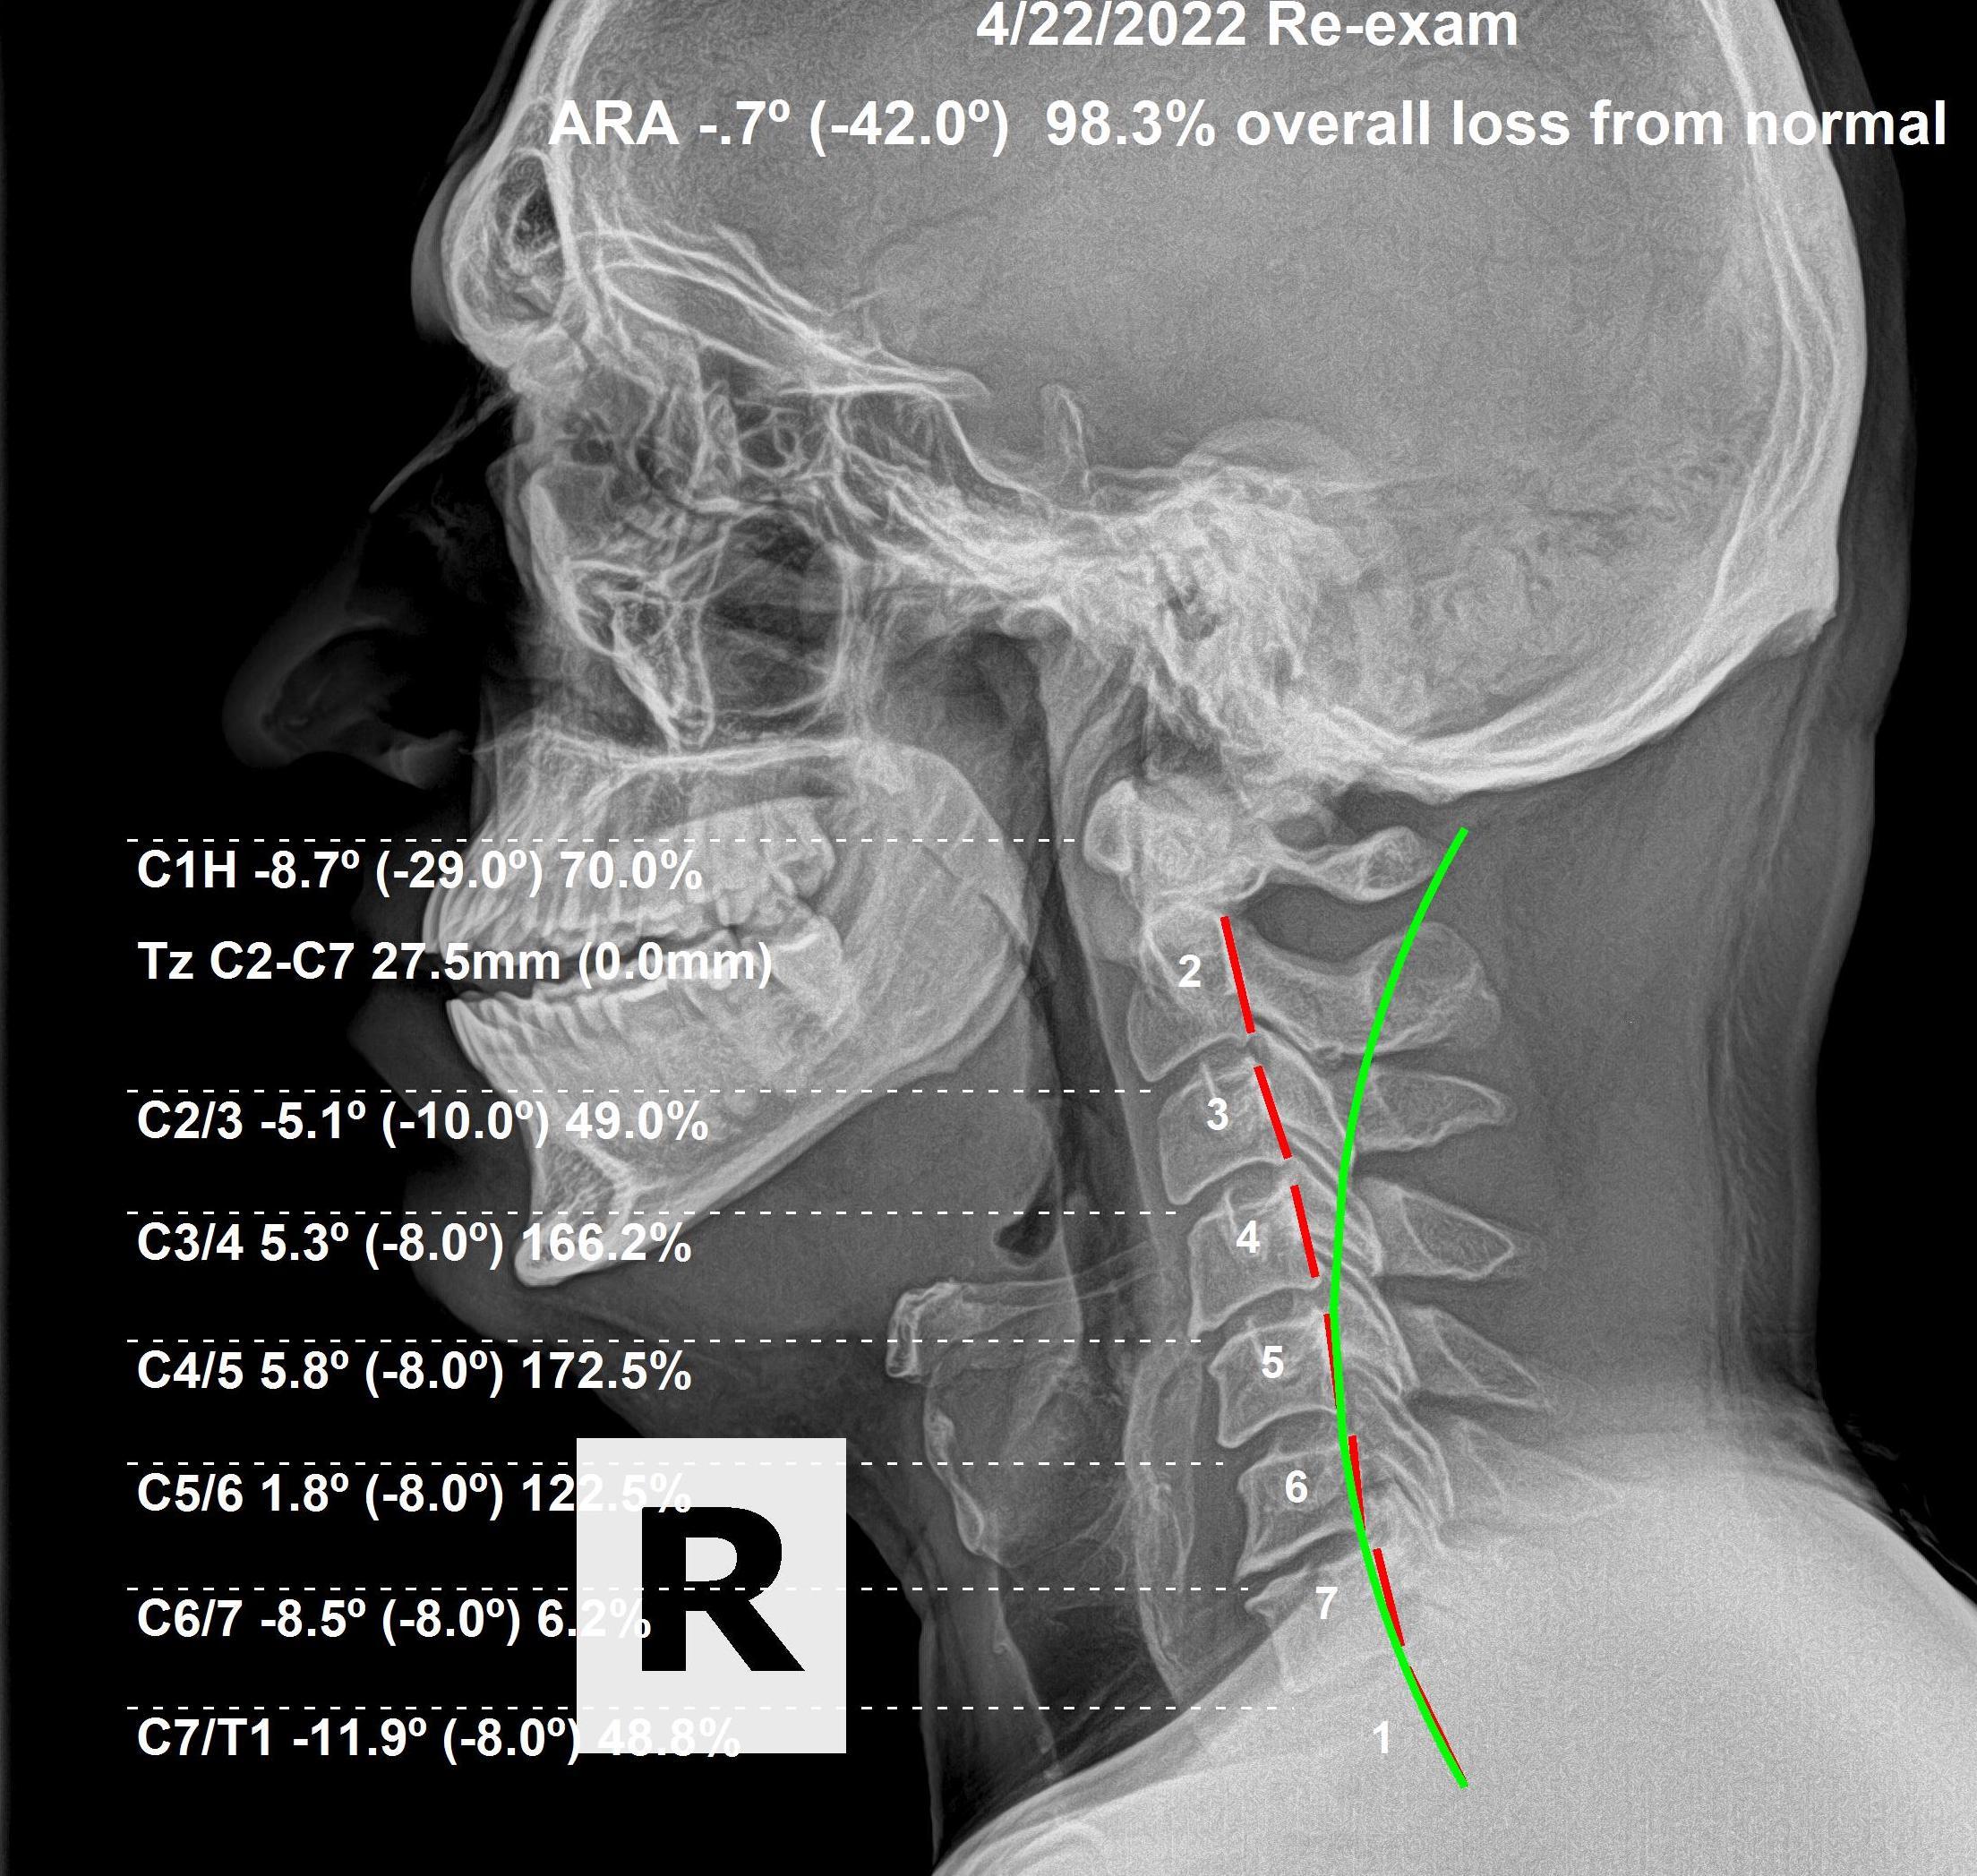

Cervical Spine Subluxations and Neck Pain

What does neck pain have to do with Chiropractic Care? Neck pain is an extremely common problem, with an estimated two-thirds of the population experiencing it at some point in their lives. While there can be many causes, spinal subluxations in the cervical vertebrae are underlying cause. Thankfully, chiropractic care and adjustments of the upper…